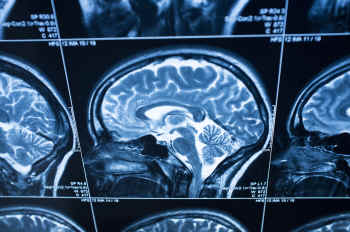

The brain is an immensely complicated, indispensable organ. Virtually every function is controlled by the brain – it is the body’s command central. Understanding its workings is essential to curing a wide-range of diseases, including Parkinson’s, Alzheimer’s, traumatic brain injury, epilepsy, post-traumatic stress disorder, and neuro-psychiatric illnesses.

Truly effective study of the human brain can only be done by direct examination, which can inform scientists far better than imperfect animal models.

Impressive strides are being made in studying the human brain and how it operates. These developments are done entirely without animals and show great promise for new therapies in treating brain disorders.

For the first time, scientists have elucidated the functional differences between the autistic and non-autistic brain. Using data collected from 523 autistic people and 452 controls, and a newly developed method for analyzing MRI scans, known as Brain-Wide Association Analysis (BWAS), researchers at the University of Warwick have created a panoramic, 3D model of the human brain.

BWAS is a powerful integration of MRI and computer science, with the capability to analyze well over a billion individual pieces of data covering 47,636 areas of the human brain.

The Warwick study allowed researchers to compare computer models of autistic and non-autistic brains, identifying key brain regions relating to autism. BWAS has the potential to be applied to other cognitive brain disorders, including ADHD and schizophrenia.